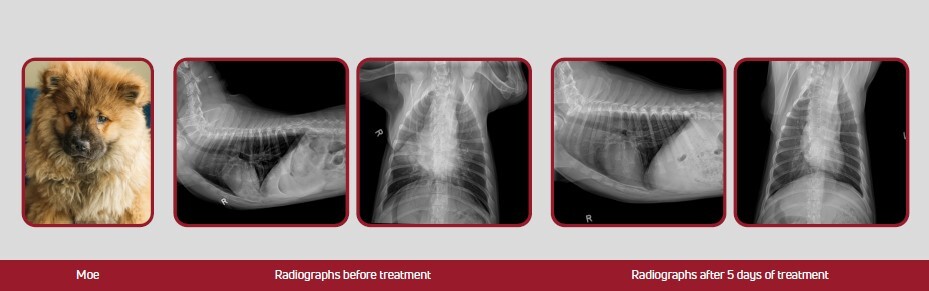

In this case study, a 14-week-old Chow Chow puppy with pneumonia named Moe showed rapid improvement after receiving laser therapy alongside antibiotics and nebulization. Within two days, his appetite and energy returned. Follow-up radiographs showed significant improvement after five days, and the patient recovered completely.

"Moe" the Chow Chow

Radiographs Before Treatments

Radiographs After Five Days of Treatment